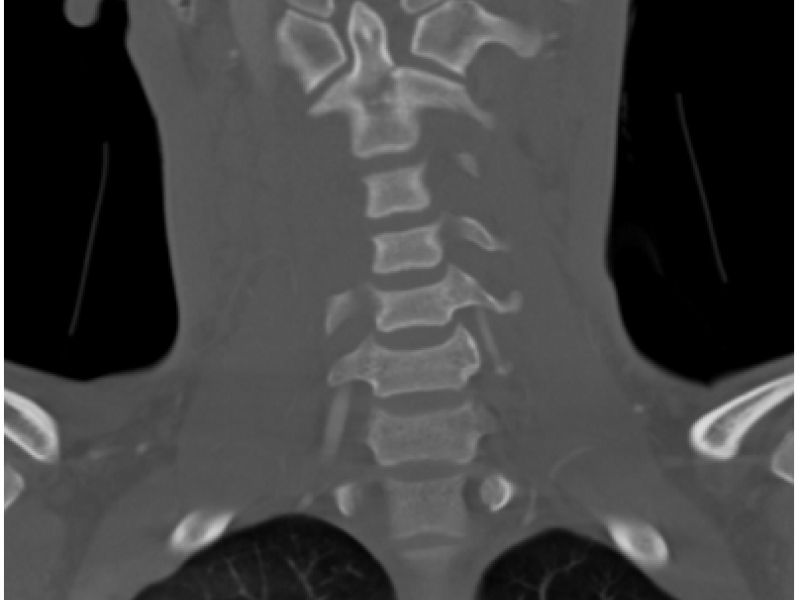

An 18 y/o M restrained driver is rear ended in a high speed